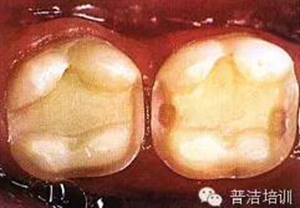

三、牙體預(yù)備完成,,邊緣預(yù)備短斜面(45度),短斜面這點(diǎn)很多書(shū)上沒(méi)具體說(shuō),想想還是有必要的,但在金屬嵌體和瓷嵌體就沒(méi)必要了。其實(shí)預(yù)備這一步驟沒(méi)什么高深莫測(cè)的,多加訓(xùn)練,端正態(tài)度就可以。

四、如果在預(yù)備過(guò)程中,有比較明顯的倒凹存在時(shí),可以在軸壁以及軸髓線角處涂一層蠟,并可作為樹(shù)脂水門(mén)汀預(yù)留在空間,但不可涂抹過(guò)多。